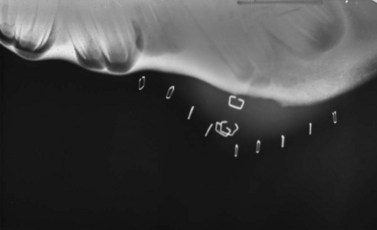

Rather than approximating the location of the tooth’s apex, using the guidelines described above, the exact site of the apex of the diseased tooth can be identified radiographically by placing radio-opaque markers, such as skin staples, in the region estimated to be near the tooth’s apex (Fig. 20.39) or by placing a blunt metallic probe into a discharging tract at the tooth’s apex.22 The primary X-ray beam must be approximately perpendicular to the longitudinal and transverse axes of the head because even slight deviation of the beam from a plane perpendicular to these axes markedly distorts the image, which could result in parallax distortion and inaccurate identification of the site for osteotomy. To see the interproximal dental spaces, the X-ray beam can be deviated slightly rostrally or caudally from perpendicular to the longitudinal axis of the head so that the beam is aligned perpendicular to arcades. Multiple views should be taken until the precise position for the surgical approach is identified with confidence. (See Ch. 13, Dental imaging, for more detail.)

image

Fig. 20.39 The proper site for osteotomy can be identified radiographically by placing radio-opaque markers, such as skin staples, in the region estimated to be near the tooth’s apex.